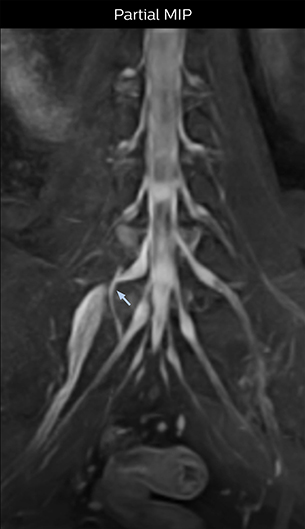

“In patients with lower extremity neurological symptoms, NerveVIEW helps us to determine the disease matching the patient’s symptoms by directly visualizing the nerves. We use the sequence mainly, when there is suspicion of intraforaminal stenosis, extraforaminal stenosis or lateral disc herniation, which is often based on routine T2- and T1-weighted images. Additionally, the excellent depiction of the course of nerves makes NerveVIEW a good navigator when applying treatment such as block therapy or surgery.”

“For example, in sagittal images, when the presence of fat is observed in the intervertebral foramen, it suggests that there is a margin around the nerve. Similarly, the absence of fat indicates that the nerve is being compressed. So, we used to deduce nerve compression indirectly. With NerveVIEW, however, we can observe the condition of the nerves directly, regardless of the presence or absence of fat. We always prefer such direct observation of anatomy over having to make an inference about it.”

“NerveVIEW is really useful for those cases where a nerve disorder is strongly suspected based on the clinical examination but our regular MRI images do not show any findings. These atypical herniations and spinal canal stenosis, occurring in 5% to 15% of the total lumbar herniation/stenosis cases are our main target when using NerveVIEW,” says Dr. Yabuki.

“Although symptoms of typical disc herniation and atypical hernia are very similar, the actual site of herniation is different. It is therefore important to characterize the nerve’s condition both inside and outside of the intervertebral foramina.

“Conversely, if we see no abnormality in NerveVIEW, we can assume at least that there is no severe condition that requires surgery. Like this, it can help us avoid unnecessary surgery. NerveVIEW can have a tremendous impact in this way.”

“Recently, the two surgical methods extreme and oblique lateral interbody fusion (XLIF and OLIF) have become mainstream for minimally invasive treatment of lumbar spinal canal stenosis and intervertebral foramen stenosis. With these surgical techniques, the spine is approached from the flank, and prior knowledge of the exact anatomy of the lumbosacral plexus would be extremely helpful. To that end, high slice resolution (less than 1 mm acquisition) that enables sharper sagittal MPR images will be needed.”

Because the obtained NerveVIEW images often exhibit a high signal in the intervertebral discs, we use partial MIP images to eliminate such intervertebral disc high signals. MIP image generation is based on the  center of the coronal stack, and RAO (right anterior oblique) and LAO (left anterior oblique) images rotated in the range of 45 degrees are used for diagnosis.